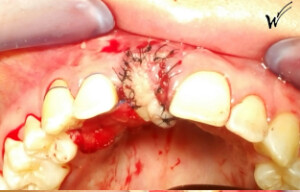

Après la guérison des tissus mous (gencive) et durs (os alvéolaire), la couronne céramique esthétique a été installée sur l’implant.

Le maintien de l’esthétique du sourire dépend en grande partie de la reconstruction des tissus gingivaux entourant la couronne céramique esthétique et de l’os autour de l’implant.

Cicatrisation des tissus et résultat clinique à la pose de la couronne céramique